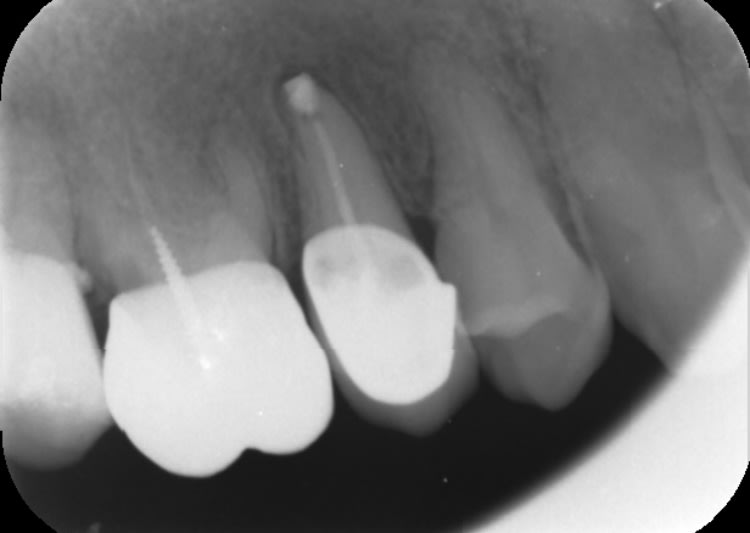

je vous tiens au courant de mon cas pour ma 37 en ERI. Belle diminution de la lésion, le seul truc c'est que le patient perd patience ...alors décision: je m'en ressers pour pilier de bridge ou pas ?

je vous joins les cones beam de juin 2019 avec la lésion initiale et celui d'aujourd'hui.

la première 3D date de juin 2019

Avant , et 1 an après